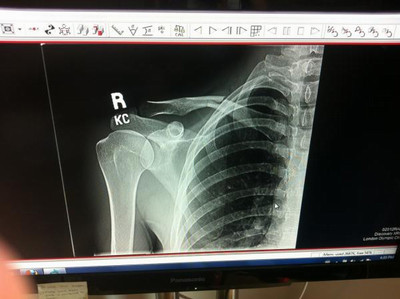

2/ Emily Batty. Byla jednou ze širší skupiny adeptek na medaili. Kanaďanka ale závod dokončila až jako čtyřiadvacátá. Není divu, závod totiž absolvovala se zlomenou klíční kostí. Zranění si přivodila už v úterý při prvním tréninku na olympijské trati. "Strašně jsem dřela, abych se do Londýna dostala, nechtěla jsem si to zkrátka nechat ujít," řekla Emily.